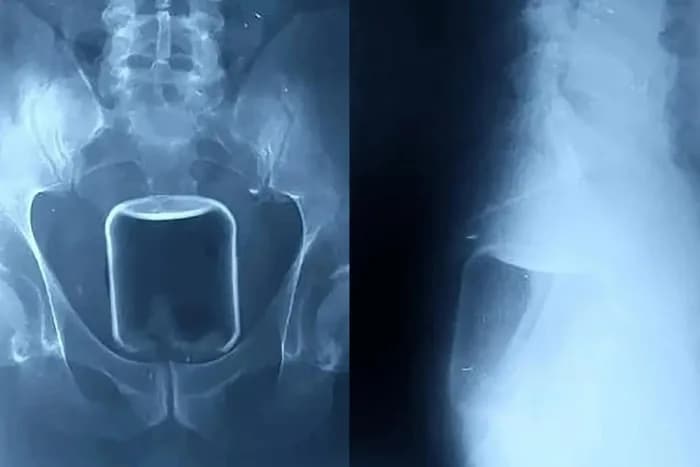

Imagens de raio-X divulgadas pelo hospital mostram o copo de vidro alojado na parte superior do reto e avançando em direção ao intestino superior.